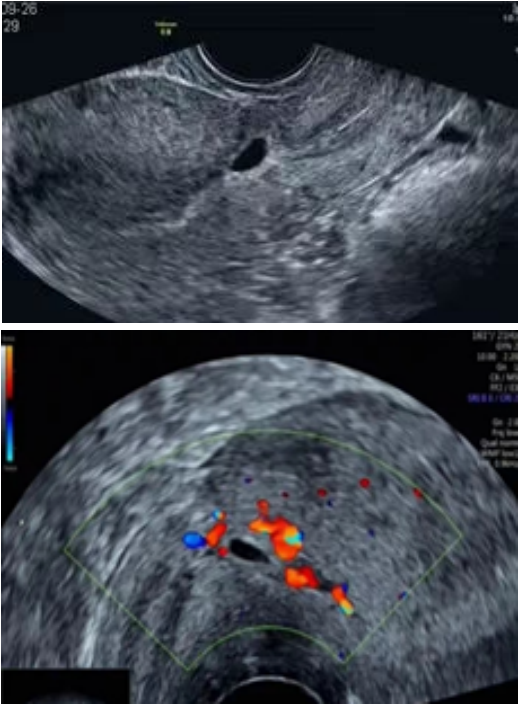

面对瘢痕妊娠,超声发挥不可替代的作用,阴道彩超是诊断瘢痕妊娠的首选方法,首次超声检查建议在孕8周前进行,明确妊娠囊与瘢痕位置关系。

根据超声妊娠囊(CSP)的不同超声表现,将其分为以下三种类型,其声像图特征分别如下:

🔹I型

妊娠囊部分着床于子宫瘢痕处,部分或大部分位于宫腔内,少数或达宫底部宫腔;

• 妊娠囊与膀胱间子宫肌层厚度>3mm

• CDFI:瘢痕处见滋养层血流信号(低阻血流信号);

• 此型囊胚着床于无缺损的瘢痕上。